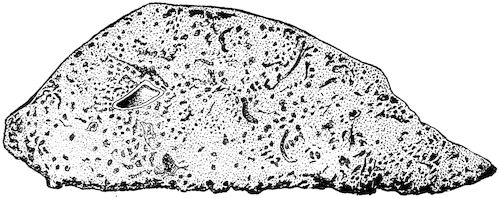

Fig. 8.—Transverse section through the middle region of the face in a pig suffering from osseous cachexia.

18In the final stages, the bones may be cut with a knife, and a time arrives when bony tissue seems completely to have disappeared; thus, as shown in Fig. 8 herewith, it was possible to cut the entire head of a pig into thin slices without the slightest difficulty. All parts of the head had been affected by the softening change.